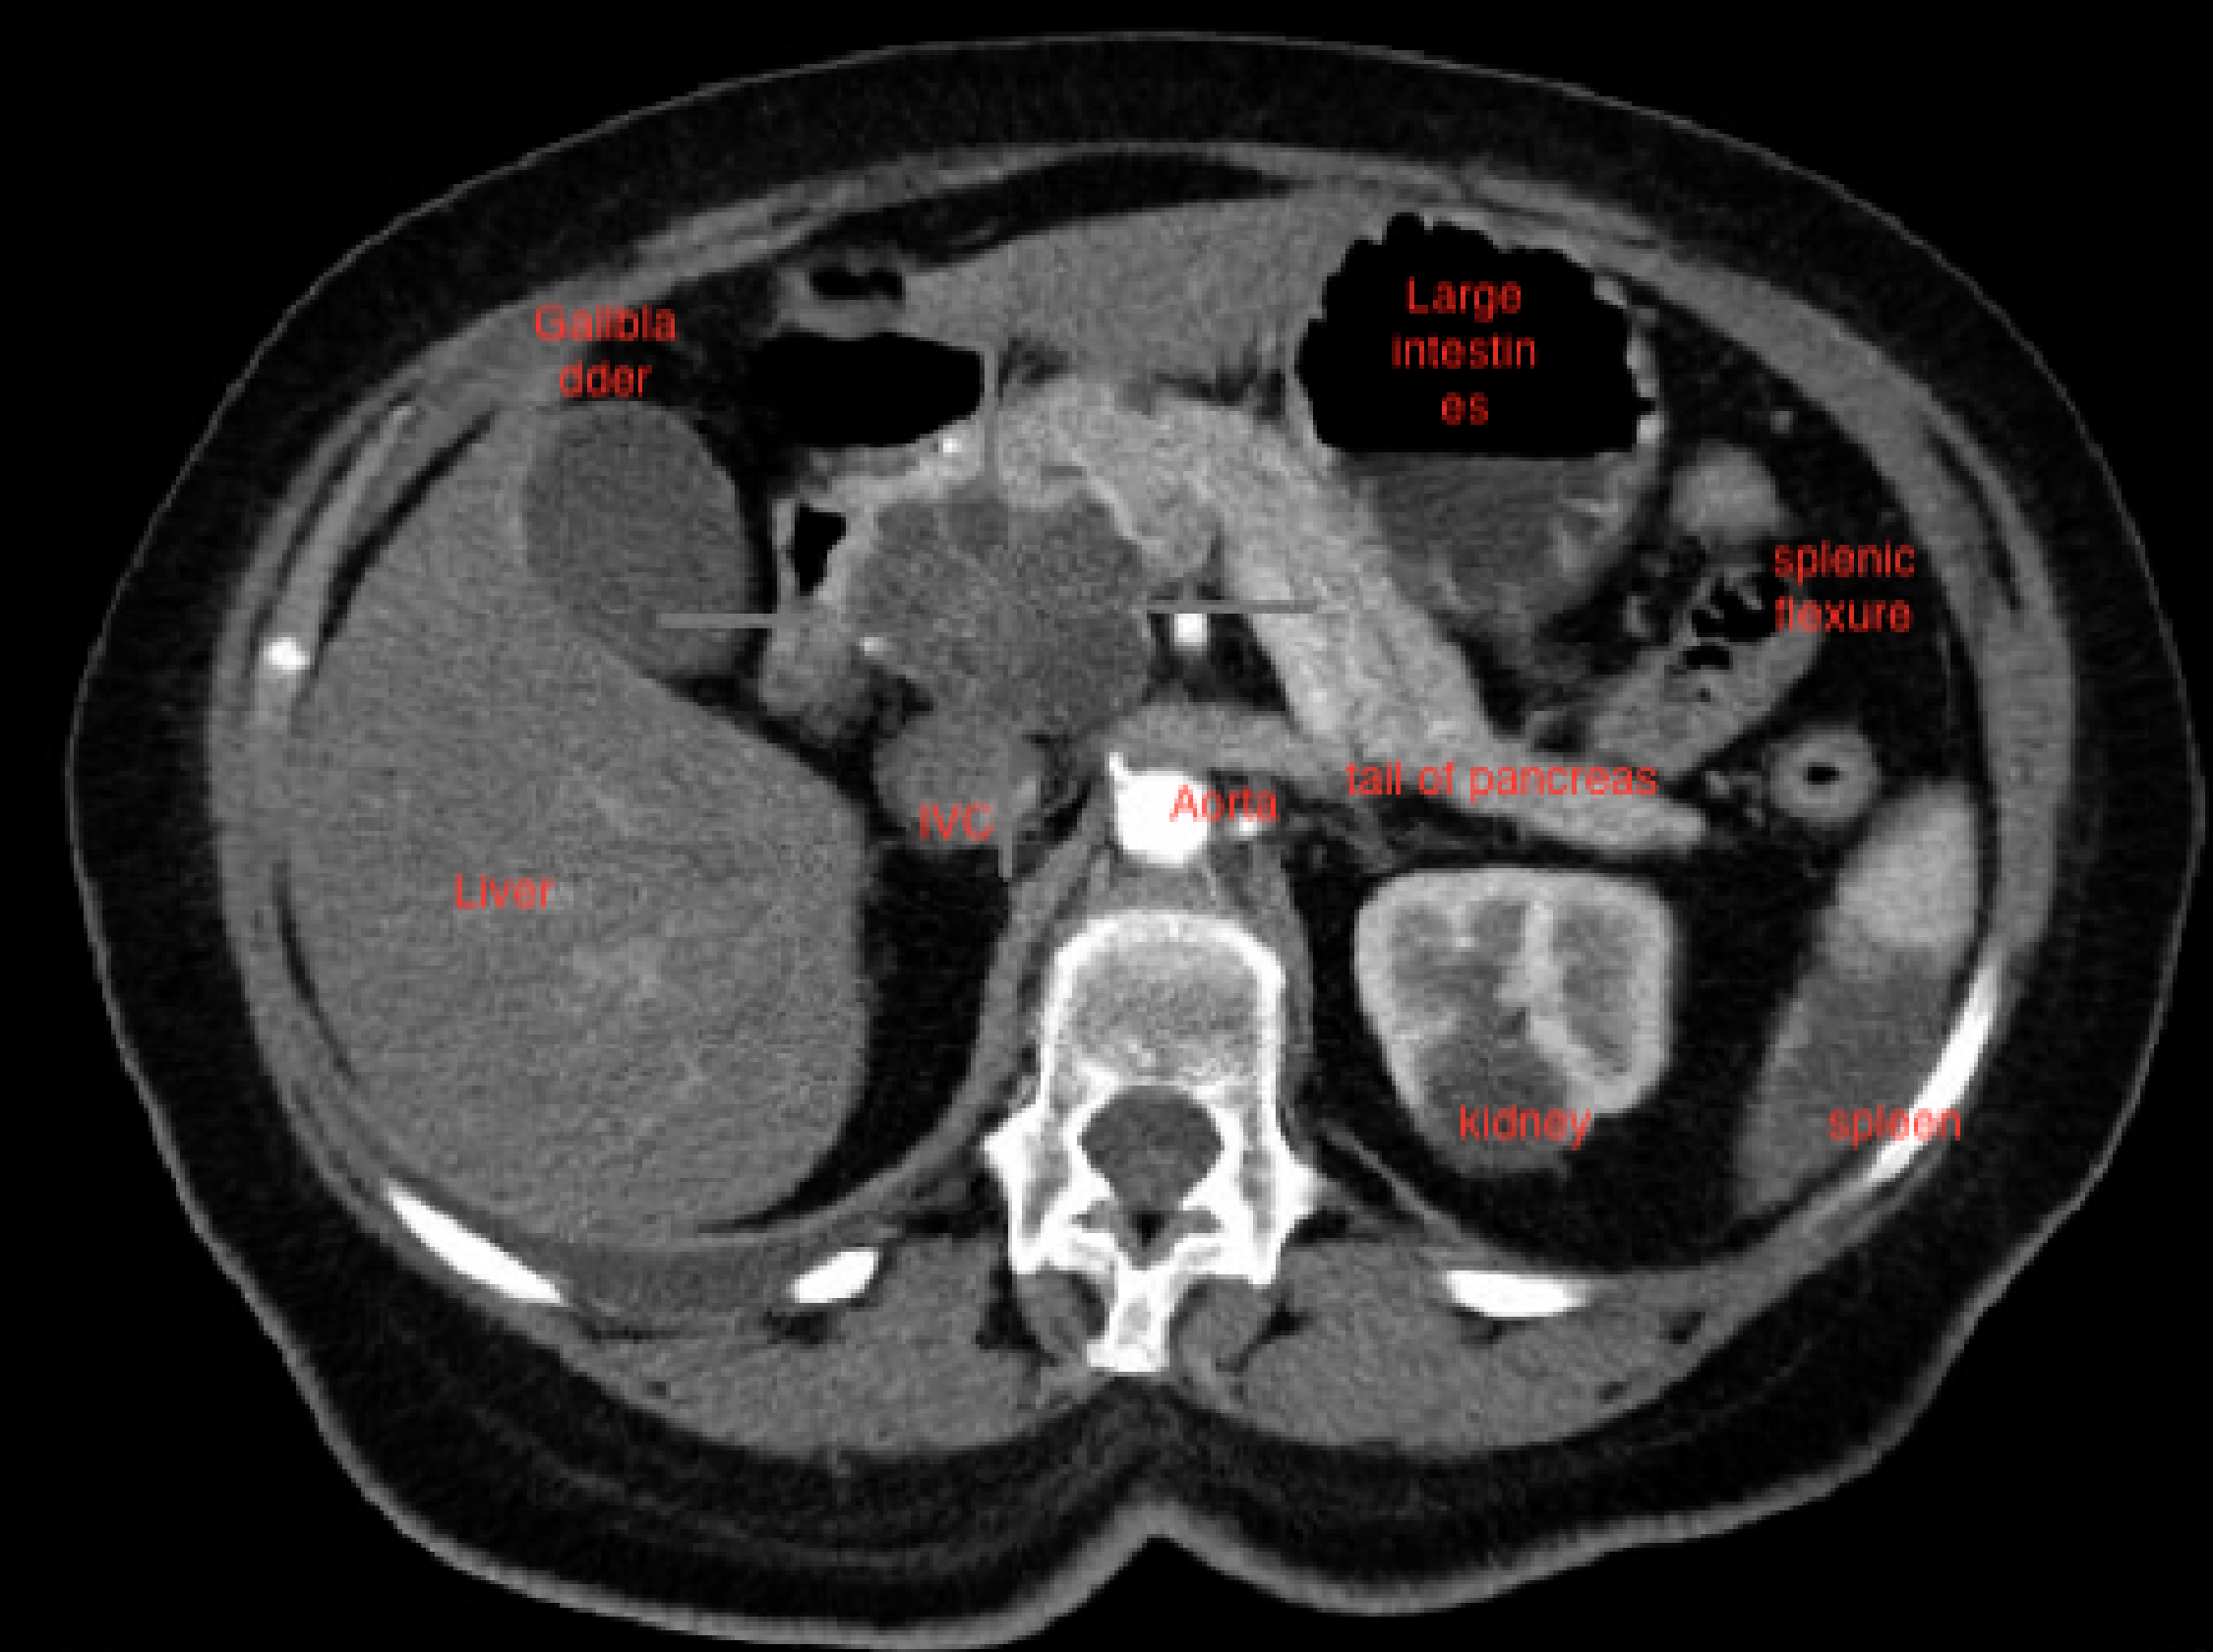

e) Computed tomography (CT): contrast enhanced CT scan can be used to identify and stage hepatic, bile duct and pancreatic tumors in obstructive jaundice due to these tumors.

CT scan showing tumor in the head of pancreas

(b) CT scan showing dilated intrahepatic ducts (arrows) in the liver.